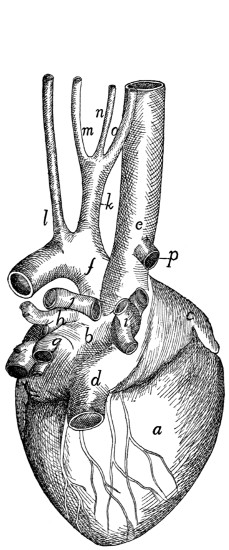

| 115. |

Heart |

276 |

| 116. |

Heart |

276 |

| 117. |

Inside of Heart |

278 |